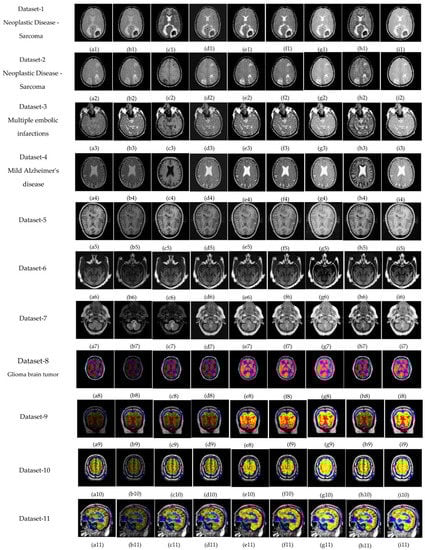

The subjective evolution is carried out on various input datasets as shown in Figure 3. In this paper, five groups of datasets have been used. The group 1 input images are MR-T1–MR-T2 datasets as shown in Figure 3((p1–p4) and (q1–q4)). Group 2 input images are MR-T1 and MRA as shown in Figure 3((p5) and (q5)). Group 3 input images are MRI and CT in Figure 3((p6–p7) and (q6–q7)), and group 4 input data set images are MRI and PET in Figure 3((p8–p11) and (q8–q11)). Finally, group 5 input images are MR-T2 and SPECT datasets as shown in Figure 3((p12–p16) and (q12–q16)). In this article, the performance of the proposed fusion scheme is compared with various existing algorithms, namely, the PCA method, Naidu’s [52] method, Sanjay’s [29] method, contourlet transform (CONT) method, Chaira’s IFS [53] method, Bala’s IFS [54] method, Sugeno’s IFS [55] method, and Zhu’s [56] method are in Figure 4. The fusion results of the PCA method-based fusion images are shown in the first column in Figure 4(a1–a16), DWTPCA method-based fusion images are displayed in the second column in Figure 4(b1–b16), DWT with fuzzy method-based fusion images are shown in the third column in Figure 4(c1–c16), CONT method based fusion images are displayed in the fourth column in Figure 4(d1–d16), Chaira’s IFS-method based fusion images are shown in the fifth column in Figure 4(e1–e16), Bala’s IFS method based fusion images are displayed in the sixth column in Figure 4(f1–f16), Sugeno’s IFS-method based fusion images in the seventh column in Figure 4(g1–g16), PC- NSCT method based fusion images are in the eighth column in Figure 4(h1–h16). Finally, the proposed fusion images are exhibited in the last column in Figure 4(i1–i16). Subjective analysis is related to human perception, and the proposed fusion method proves, the fused image has greater contrast, luminance, and better edge information than other existing methods, and clear tumor regions are shown in Figure 4((i4), (i8), (i12), (i13), and (i16)).

Figure 3.

Medical image datasets: (p1–p4) and (q1–q4) are MR T1–MR T2 input images: (p5) and (q5) are T1 weighted MR–MRA input images; (p6,p7) and (q6,q7) are MRI–CT input images; (p8–p11) and (q8–q11) are MRI–PET input images; and (p12–p16) and (q12–q16) are the MR-T2–SPECT input images.

The proposed fusion results show that the quality of the fused image is better than other existing fusion methods. Among all the groups of medical image datasets, the first group of medical image datasets are T1–T2 weighted MR images. Fusing these two images shows soft tissue and an enhanced tumor region. The second group of medical image datasets are MR-T1and MRA images. MR-T1 images produce delicate tissue data but do not detect the abnormalities in the image, while the MRA image easily detects the abnormalities but due to low spatial resolution, is unable to produce the tissue information. Fusion of these images (MR-T1 and MRA) shows the complementary information with detailed lesion locations in the fused image.

The third group dataset consists of MRI and CT images, which are taken from reference [44]. MRI imaging produces delicate tissue data, while CT imaging gives bone information. The combination of these two images produces a quality fused image, which will be more useful for the diagnosis of disease. The fourth and fifth medical image datasets are MRI–PET and MR-T2–SPECT images. The fusion of these combinations to get more complementary information is achieved in a fused image and highlights the tumor regions, which will be helpful for medical-related problems.